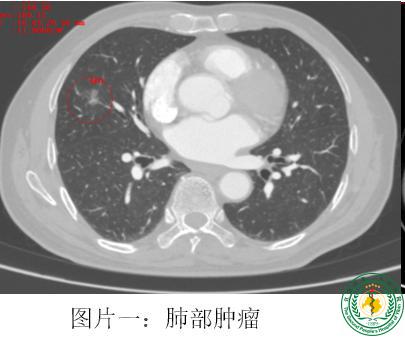

患者王大爷,因进行性吞咽吞咽梗阻感4月余入院,外院确诊食管恶性肿瘤,住院期间完善胸部检查提示右肺中叶有两个结节,结合CT影像学考虑早期肺癌可能性较大需行肺叶切除。患者家属反复要求行微创手术,希望能同期处理食管和肺部肿瘤。但是微创食管癌手术和肺癌手术的切口有所不同,同期微创行食管联合肺癌根治手术增加了手术难度,尤其是单孔手术。该手术难点主要在于:1、切口选择问题,一个切口同时要做食管癌和肺癌手术,增加了操作难度。2、手术时间延长,可能增加术后并发症风险;此外,历史数据显示,同时进行肺叶切除术和食管癌根治术可能增加吻合口漏的风险,目前该手术在国内仅有少数几家医院能开展。但该手术对患者也可带来不小的好处:1、一次手术解决两种疾病,减轻了患者的经济负担。2、减小分次手术给患者带来的痛苦。最终,经过科室的讨论,为兼顾微创及缩短手术时间,决定为患者实施单操作孔下食管癌联合肺癌根治术。